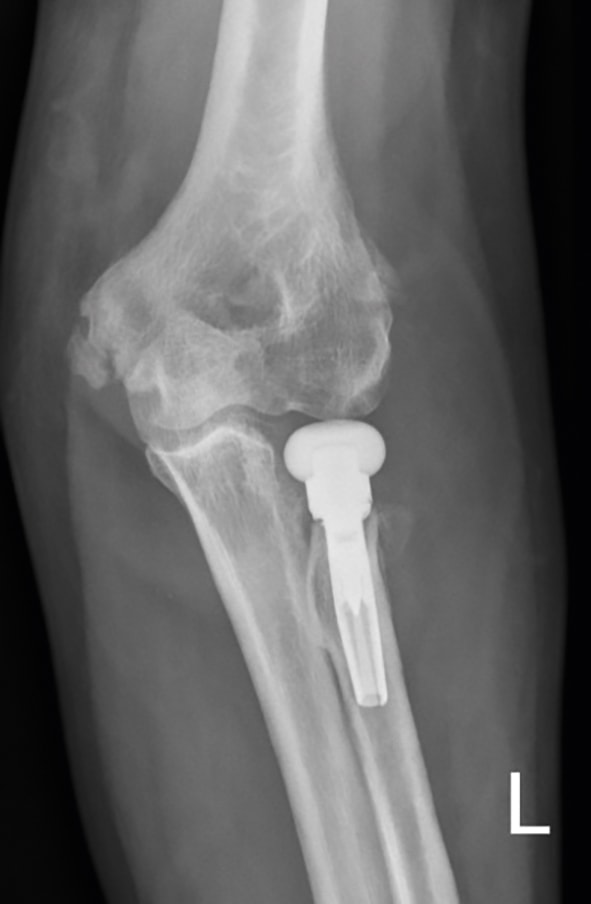

Ein 55-jähriger Bauarbeiter stürzte im Juli 2019 von einem Gerüst. Dabei zog er sich unter anderem eine multifragmentäre Radiusköpfchenfraktur und eine Spitzenfraktur des Processus coronoideus links zu (Abb. 6a). Eine operative Indikation war somit gegeben. Aufgrund der präoperativen Labordiagnostik wurde eine hyperglykämische Stoffwechsellage diagnostiziert, die prioritär behandelt werden musste. Während des konservativen Verlaufes entwickelte sich eine massive Bewegungseinschränkung und zunehmend Schmerzen beim Bewegen. Die initial geplante Operation wurde schlussendlich im Dezember durchgeführt. Es wurde eine Arthrolyse durchgeführt und das frakturierte Radiusköpfchen durch eine endoprothetische Versorgung ersetzt (Abb. 6b). Im ambulanten Setting erhielt der Patient wöchentlich dreimal Physiotherapie und 8 Wochen postoperativ eine statische Quengelschiene. Anfang März 2020 trat der Patient in die stationäre Rehabilitation durch den Autor ein. Die Schmerzsituation hatte sich deutlich verbessert, aber es hatte sich eine hartnäckige Bewegungseinschränkung vor allem in Ellbogenflexion manifestiert. Die aktive Beweglichkeit im Ellbogen links belief sich bei Eintritt bezüglich Flexion/Extension auf 80/10/0, bezüglich Pronation/Supination auf 80/0/80 (aus 70° Ellbogenflexion), passiv in Flexion/Extension auf 85/10/0, bezüglich Pronation/Supination auf 85/0/85. Das Endgefühl in Ellbogenflexion war fest-elastisch (eher kapsulär), und der Patient berichtete über gelegentliche Parästhesien in der linken Hand. Die statische Quengelschiene versuchte er in der Nacht in endgradiger Flexion zu tragen. Der Patient stellte sie jeweils so stark ein, dass er sie nur jeweils 1 Stunde lang tragen konnte und sie dann schmerzbedingt wieder abziehen musste. Die vermehrten Schmerzen zogen sich jeweils bis zum nächsten Morgen hin. Im stationären Rehabilitationsaufenthalt wurde mit 3 bis 4 Physiotherapiesitzungen pro Woche und täglich begleitenden medizinischen Trainingstherapien gestartet. Die statische wurde durch eine dynamische Quengelschiene ersetzte und die Dosierung „Quengelung in der Remodulierungsphase“ angewendet. Somit konnte der Patient die Schiene nachts 3 bis 4 Stunden lang tragen, bis es für ihn unangenehm wurde. Die morgendlichen zusätzlichen Schmerzen blieben ab dem zweiten Tag aus. Nach 3 Wochen belief sich die aktive Flexion auf 90°, die passive auf 95°. Zusätzlich wurde versucht, den nach der manuellen Mobilisation auftretenden „Jojo-Effekt“ bis zur nächsten Therapiesitzung mit einer einstündigen Quengeltherapie mit derselben Dosierung zu minimieren. Nach weiteren 2 Wochen konnten bei der Austrittsuntersuchung folgende Werte erhoben werden: aktiv bei Flexion/Extension 95/10/0 bzw. bei Pronation/Supination 85/0/80 (aus 90° Ellbogenflexion), passiv bei Flexion/ Extension 100/5/0 bzw. bei Pronation/ Supination 85/0/85 (Abb. 6c). Dies ist ein erfreulicher Fortschritt und zeigt aus der klinischen Erfahrung des Autors heraus, dass eine wundheilungsphasenadaptierte Dosierung im Einsatz mit Quengelschienen eine effektvolle Unterstützung der Manuellen Therapie darstellt. Dieses stationäre Setting wurde nun in die ambulante Nachbehandlung übertragen.